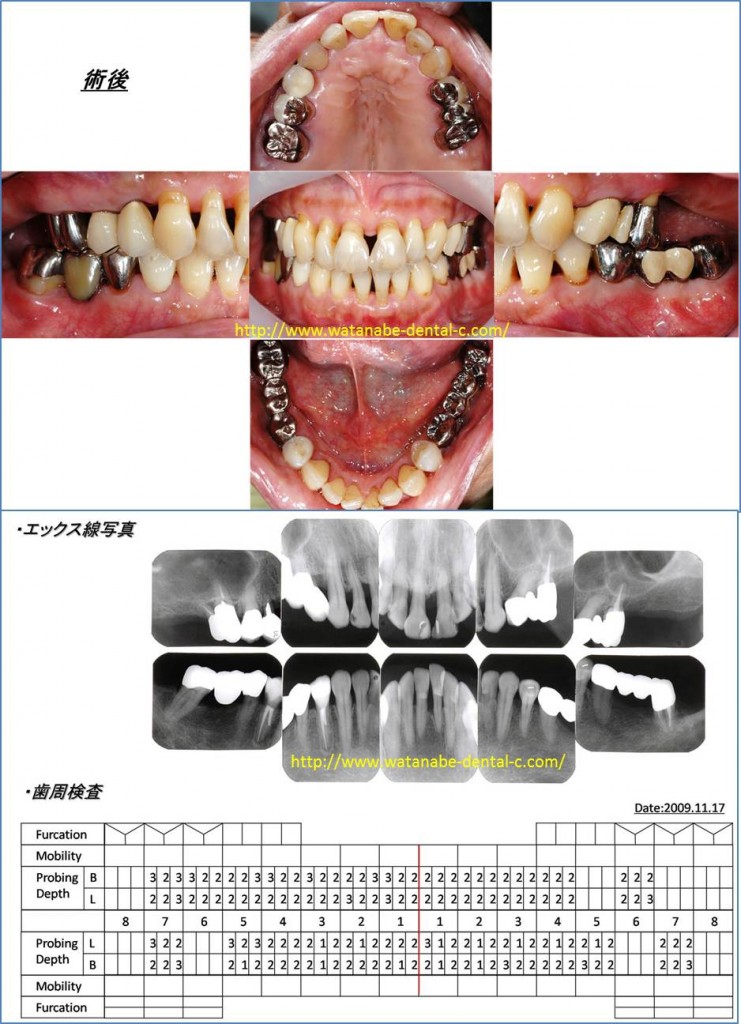

術後の写真と、歯周ポケット検査です。気になって来院された上の前歯の開きは改善しています。これは矯正治療を行ったわけではありません。上の前歯に関しては歯周外科処置も行っていません。患者さん自身の歯間ブラシ、歯ブラシ、ワンタフトブラシによるプラークの除去と来院されて行った「スケーリング・ルートプレーニング」により炎症を起こしていた因子が除去され、歯が自然と元の位置に戻りました。炎症は、歯をも動かしてしまうのです。炎症が改善すれば、歯の動揺が改善し、歯が自然と元の位置に戻ってくることがよくあります。歯周基本治療をきちんと行い、炎症を起こしている原因を除去することが最も重要になります。歯周ポケットも全体的に3mm以下に改善しました。